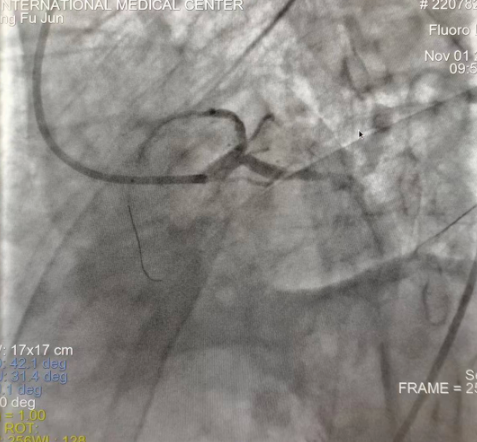

閉塞的血管再通時(shí)間取決于急救時(shí)長(zhǎng)、轉(zhuǎn)運(yùn)時(shí)長(zhǎng)和治療時(shí)長(zhǎng),在前兩方面,醫(yī)院已為患者爭(zhēng)取了最短時(shí)間?;颊呒覍龠h(yuǎn)在陜北,雖然已在趕來的路上,但最快抵達(dá)西安也要3小時(shí),在與患者家屬電話溝通同意急診手術(shù)后,醫(yī)療總值班代家屬簽字,康曉軍在請(qǐng)示心臟病醫(yī)院王海昌院長(zhǎng)及心臟內(nèi)科CCU尚福軍主任后,積極進(jìn)行術(shù)前準(zhǔn)備。在沒有家屬陪同、沒有交費(fèi)、沒有辦入院手續(xù)的情況下,患者經(jīng)胸痛中心綠色通道被送往心臟冠脈介入手術(shù)室,打通了完全閉塞的心臟前降支近段血管。